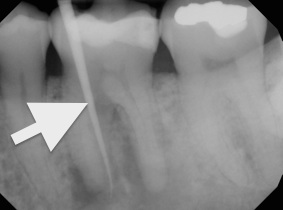

Chronic apical abscess: Radiography typically reveals a radiolucency. Clinically, there is a sinus tract present on the gingival tissue. The draining sinus tract should be traced with a gutta-percha cone and then confirmed radiographically (Figure 5 and Figure 6).

Fig 5. Clinical confirmation of the periradicular diagnosis—chronic apical abscess on tooth No. 19. The tooth is not sensitive to percussion or palpation. A gutta-percha cone is inserted into the sinus tract.

Figure 5

Fig 6. Radiographic confirmation of periradicular diagnosis—chronic apical on tooth No. 19. Note the tracing of the inserted gutta-percha to the etiology. Local anesthesia is generally not required for a sinus tract tracing.

Figure 6